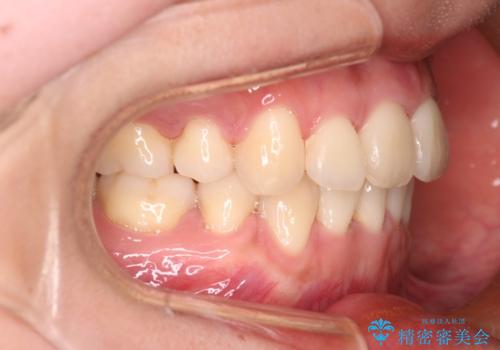

【審美装置】前歯のデコボコを綺麗に

- 上の前歯のデコボコが気になるということで来院されました。

叢生量(デコボコ)が多いため、上下左右4番目の歯を抜歯してワイヤー矯正を行う治療計画を立てました。

主訴である前歯のデコボコが改善され、噛みあわせも綺麗になりました。

歯肉退縮もなく、予定通りに治療を終えることができ良かったです。